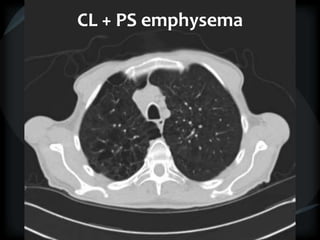

CL + PS emphysema

Hyperlucency

Centrilobular emphysema

Paraseptal emphysema

CL + PSemphysema